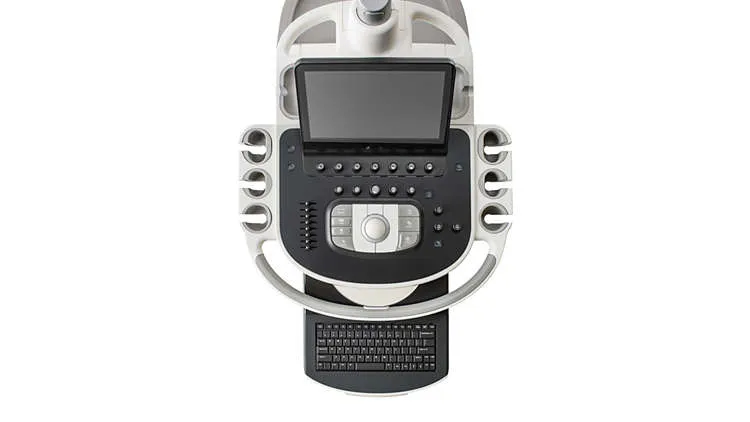

- Тип: стационарный

- ЖК монитор: 21″

- Командный сенсорный экран: 12″

- 4 активных порта для датчиков

Планшетоподобный интерфейс существенно упрощает навигацию

Быстрая навигация между функциями системы с помощью планшетоподобного интерфейса, снижающего количество нажатий кнопок на 40%, а общее количество действий на 15%.

Превосходная эргономика, позволяющая избежать возникновения туннельного синдрома

В ультразвуковой системе Philips EPIQ 5 используется панель управления и монитор на шарнирном кронштейне, что обеспечивает эргономичные условия работы врачей в любом, удобном для них положении и позволяет избежать возникновения туннельного синдрома. Широкий экран с диагональю 21,5 дюйм облегчает просмотр изображений. В системе EPIQ 5 имеется четыре разъема для датчиков, что упрощает переключение между датчиками во время исследования.